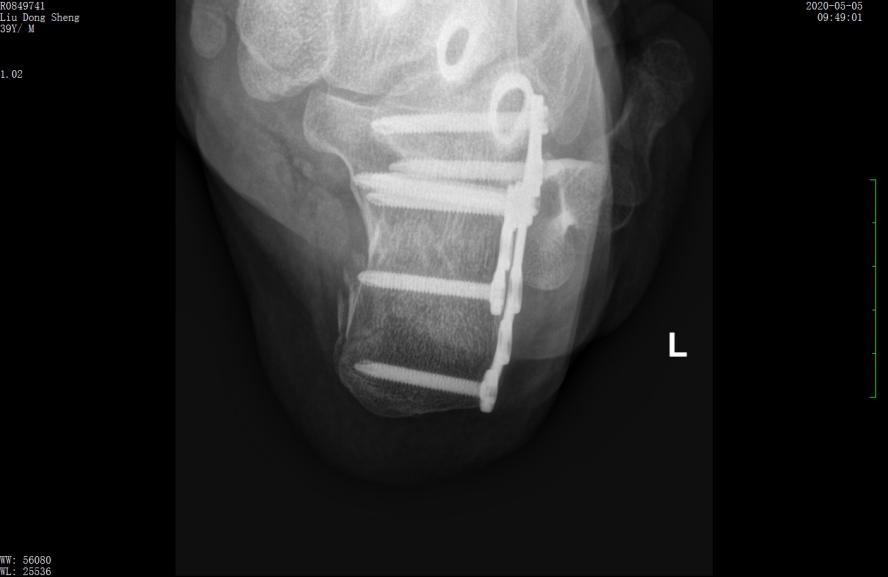

案例1影像

行微创手术治疗后,跟骨高度恢复,关节面平整